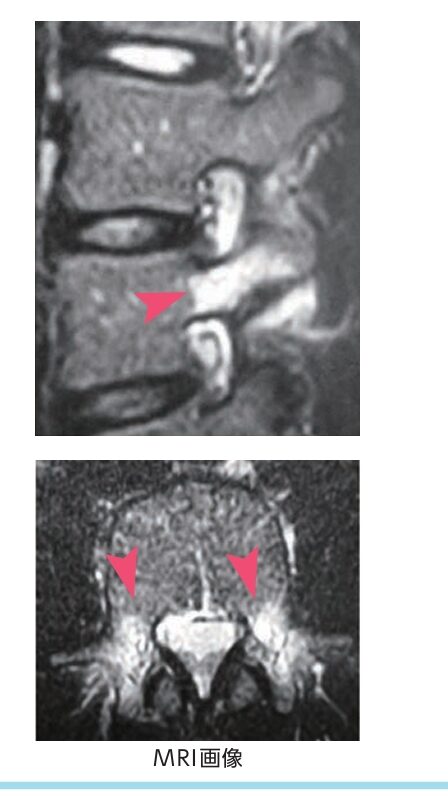

一方でMRIは磁石で撮影するレントゲン、CTとは全くことなる検査であり骨のような硬いものよりも柔らかいものの検出に優れます。

腰椎分離症も非常に初期の骨の中の出血が検出できます。

MRIでは非常に早期から骨の中の海綿骨の出血(画像で白くなっている部分)がわかります。

そのため腰椎分離症の早期診断はMRIが有用です。

CTもある程度分かりますが放射線被爆の問題もあるため被爆のないMRIが優れていると思います。